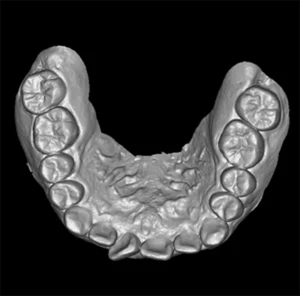

Model Scan (Optional) – Dental CBCT Support

In addition, optional model scanning allows accurate digital impressions and prosthetic planning, making this system ideal for both orthodontic and implant applications.